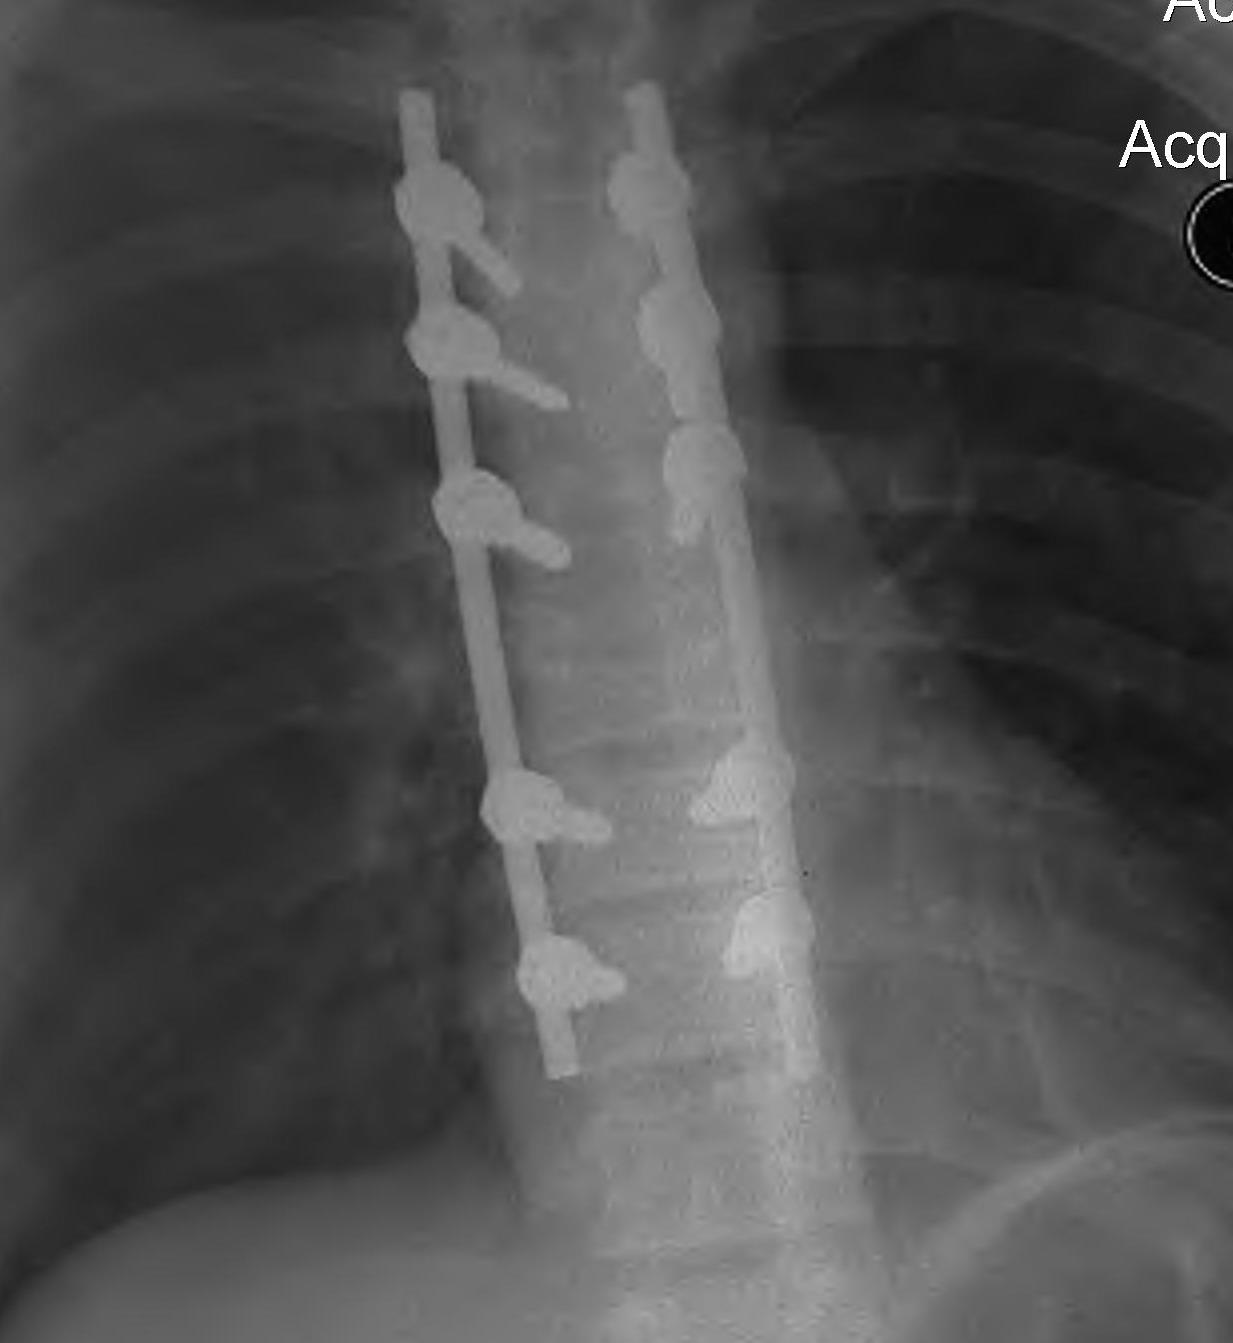

Anterior corpectomy and strut graft

Indication

- decompression of retropulsed fragments in patient with neurology

Technique

- approach as per level

- thoracoabdominal for T11 - L1

- thoracotomy for T2 - T10

- remove disc above and below and remove vertebral body

- remove fragments / need to know if 1 or 2

- screws in vertebral body above and below

- 2 screws in a lateral plane

- insert fibular strut allograft / titanium cage

- augment with cage